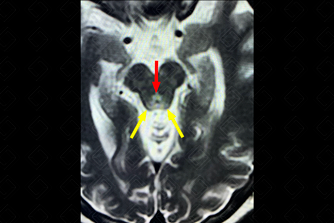

Texto alternativo para a imagem Figura 1. Créditos: Dra. Elazir Mota - Rio de Janeiro/RJ

Descrição da figura 1: Ressonância magnética do crânio, sequência FLAIR evidenciando hipersinal na placa quadrigeminal (seta vermelha e setas amarelas).

• Ressonância magnética do crânio: Diante dessa suspeita clínica, o exame de escolha deve ser a ressonância magnética por ser o único método capaz de detectar as alterações de sinal no parênquima. Observam-se áreas de hipersinal simétricas e bilaterais no T2 e FLAIR nas porções mediais do tálamo (85%), corpos mamilares (58%), teto mesencefálico ou placa quadrigeminal (35%), região periaquedutal e ao redor do 3 o ventrículo.